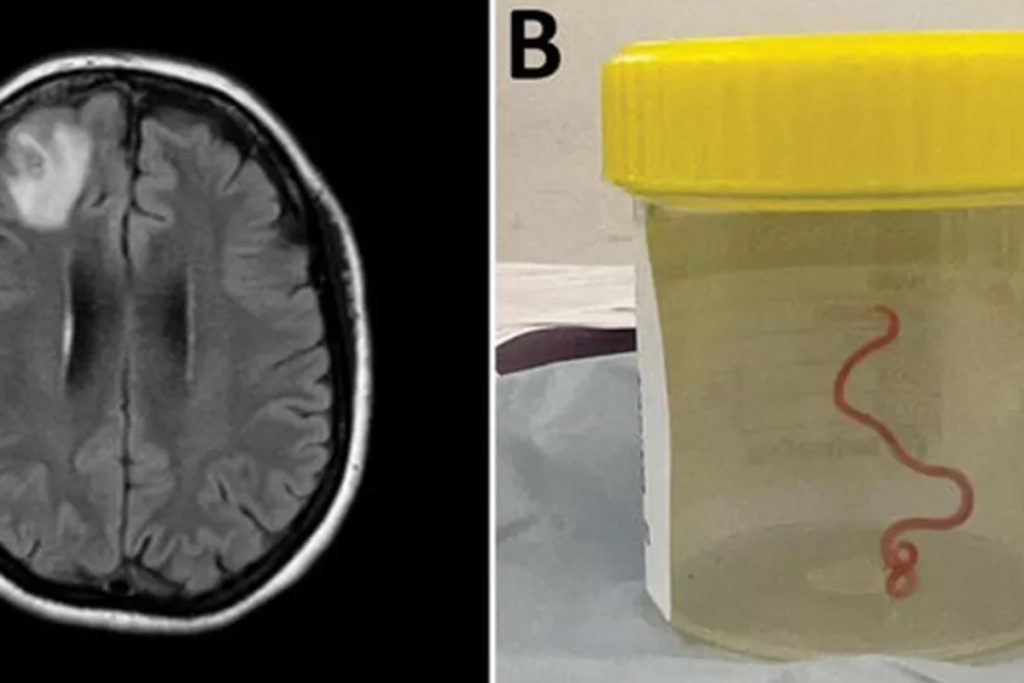

Una neurocirujana que investigaba los misteriosos síntomas de una mujer en un hospital australiano contó que extrajo del cerebro de la paciente un gusano que se retorcía.

La cirujana Hari Priya Bandi estaba realizando una biopsia a través de un agujero en el cráneo de la paciente de 64 años en el Hospital de Canberra el año pasado cuando utilizó unas pinzas para sacar el parásito, que medía 8 centímetros.

La criatura era la larva de un gusano redondo autóctono de Australia, llamado Ophidascaris robertsi, que hasta ahora no se conocía como parásito humano. Estos gusanos son comunes en las pitones de alfombra.

El gusano todavía se retorcía (via AP)